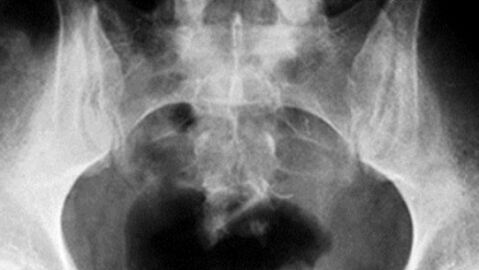

24 Gegenstände, die im Rektum von Patienten gefunden wurden

Hier geht es zu den 24 Bildern Hier eine Auswahl von 24 Fremdkörpern, die Ärzte aus dem Enddarm ihrer Patienten holen mussten... Nachdem du diese Bildergalerie gesehen hast, brennt dir nur eine Frage auf der Zunge: WARUM?